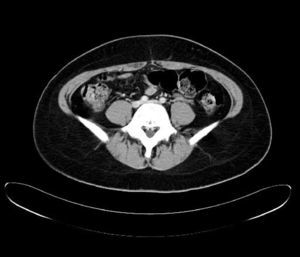

Durante el estudio le fue realizado una TAC que encontró tromboembolismo pulmonar bilateral sin repercusión clínica y trombosis venosa profunda de vena ilíaca izquierda, con síndrome de May-Thurner, como hallazgos casuales. El estudio de trombofilia familiar fue negativo. Se inició a continuación tratamiento anticoagulante. Recibió el alta con pauta de acenocumarol, de prednisona y levofloxacino, con mejoría clínica paulatina en las siguientes semanas (figs. 1 y 2).

Durante el estudio de la agranulocitosis de esta paciente se realizó una TAC, con el hallazgo casual de trombosis pulmonar bilateral con trombosis venosa profunda de la ilíaca común izquierda con un síndrome de May-Thurner. La paciente no refirió disnea ni otros síntomas respiratorios. Como antecedente de interés, la paciente estaba en tratamiento anticonceptivo hormonal oral y fumaba 3 cigarrillos al día, sin haberse encontrado alteraciones genéticas de la coagulación.

El síndrome de May-Thurner consiste en la compresión de la vena ilíaca común izquierda por la arteria ilíaca común derecha. Su prevalencia real es desconocida, aunque según diferentes estudios aparece entre 2-5% del total de pacientes con trastorno venoso en la extremidad inferior izquierda, y entre 18-49% de los que padecen una TVP. Este síndrome suele cursar con edema en la extremidad inferior izquierda, y suele aparecer más frecuentemente en mujeres entre los 20 y 50 años. En ocasiones puede dar lugar a complicaciones como en este caso como el tromboembolismo pulmonar.

Este síndrome fue descrito por May y Thurner en 1956 tras examinar 430 cadáveres7. La fisiopatología de la trombosis venosa profunda a nivel de la vena ilíaca común izquierda se explica por el daño endotelial debido a los microtraumatismos repetidos provocados sobre el endotelio venoso por la pulsación arterial sobre la vena. El aumento de presión intraabdominal (Valsalva) junto con un defecto de la íntima podrían intervenir como factores etiopatogénicos de la rotura de la vena. El método diagnóstico de elección hasta ahora había sido la venografía ilíaca, que permite demostrar tanto la compresión de la vena ilíaca como la toma de gradientes de presiones y la presencia de circulación colateral. Actualmente, tanto la angio-TC como la angio-RM venosa se han convertido en las técnicas diagnósticas alternativas8. El tratamiento de estos pacientes, además del tratamiento de anticoagulación, es endovascular (angioplastia con parche venoso y endoprótesis), para eliminar el trombo y la causa anatómica del problema9,10.